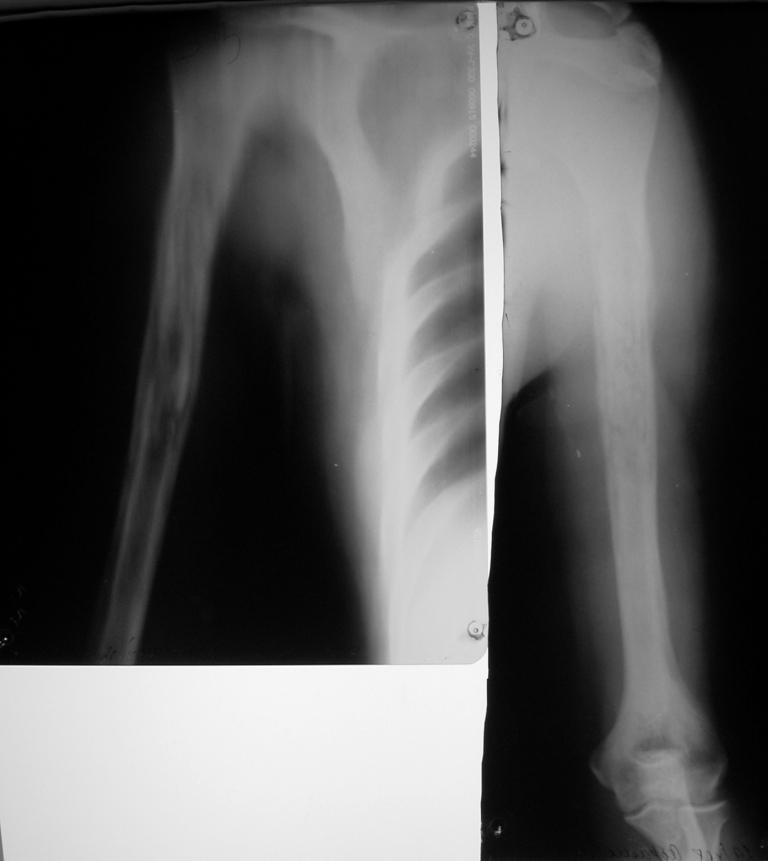

К "гнойным хирургам" обратился больной 1982 г. р.

После ушиба мягких тканей в сентябре сего года и применения тепловых

процедур через 3 недели открылся свищ. Подскажите что делать? Может

быть римирование костномозгового канала ppcntv цемент с антибиотиком?